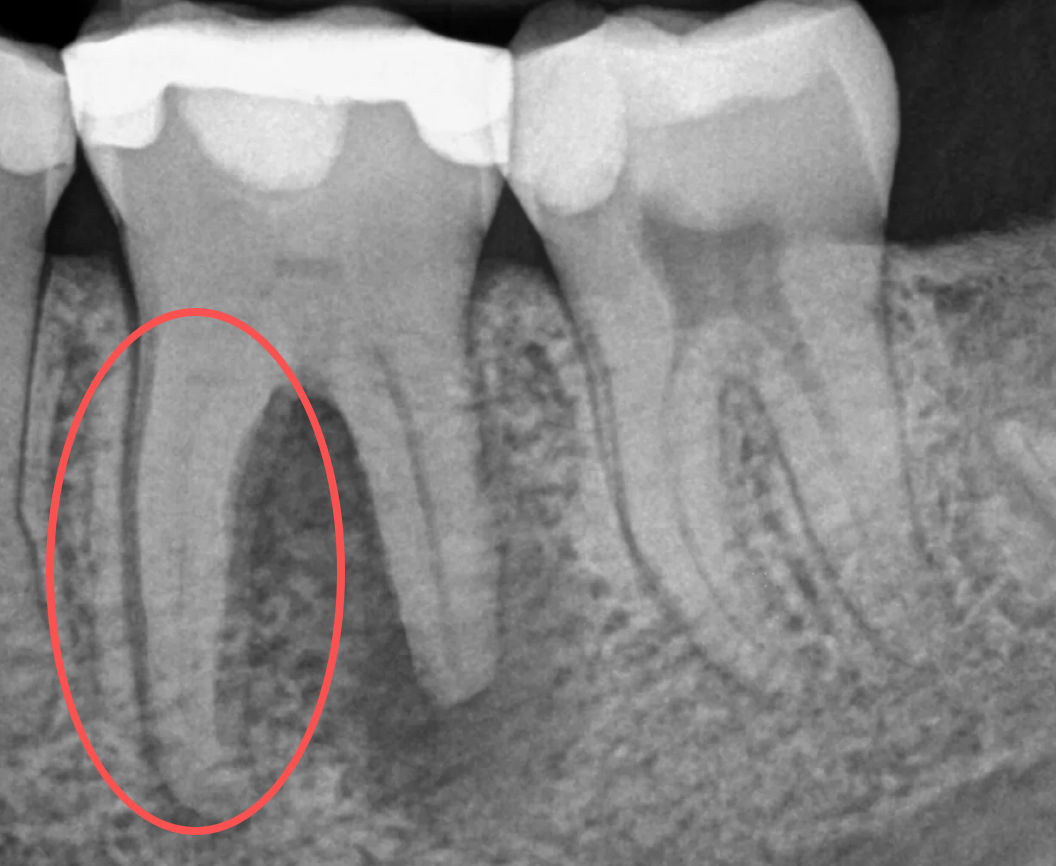

Analysisof the Etiology of Root Canal Calcification from a Dental Professional Perspective Root canal calcification is clinically characterized by canal narrowing, obliteration, and blurred or absent root canal images on radiographs. It is essentially a condition of abnormal dentin mineral deposition, which gradually fills the root canal system. This paper systematically analyzes the causes of root canal calcification from professional perspectives including dental physiology, pathology, irritating factors, age-related changes, and reparative responses.

1. Age-Related Physiological Calcification (Most Common) With increasing age, the dental pulp gradually atrophies and fibrosis, and odontoblasts continuously secrete mineralized matrix slowly. Manifested as deposition of secondary dentin, leading to reduced root canal space and narrowing of root canals.Characteristics: mostly bilateral and multi-tooth involvement with slow progression. 2. Chronic Pulpitis (Primary Pathological Factor) Deep caries, cracked teeth, attrition, and periodontal retrograde infection result in chronic pulpitis. Long-term low-grade inflammation stimulates the dental pulp and induces massive formation of reparative dentin.Commonly seen as localized calcification in single teeth, mostly starting from the apical third or coronal portion. 3. Mechanical Trauma and Microtrauma Occlusal trauma Excessive tooth preparation for fixed prosthodontics History of dental trauma (impact, biting hard objects) Mechanical irritation directly damages the odontoblastic layer and triggers a strong reparative response with rapid calcific obliteration. 4. Chemical and Thermal Irritation Irritation from restorative materials (direct restoration without base) Abnormal demineralization and remineralization caused by acid erosion Insufficient water cooling during tooth preparation leading to high temperature All these factors cause chronic dental pulp injury and promote calcification. 5. Periodontally Derived Irritation (Retrograde Root Canal Calcification) Deep periodontal pockets and periodontal-endodontic lesions Chronic periapical inflammation and alveolar bone resorption Irritants penetrate the dental pulp through the apical foramen and lateral canals, inducing calcific obliteration in the apical segment. 6. Systemic Factors (Contributing Factors) Metabolic disorders: hypercalcemia, abnormal parathyroid function Genetic predisposition: inherent tendency of dental hard tissue mineralization in some individuals Systemic medications or diseases affecting pulp blood flow and mineralization regulation Systemic factors mostly serve as aggravating factors rather than independent primary causes.